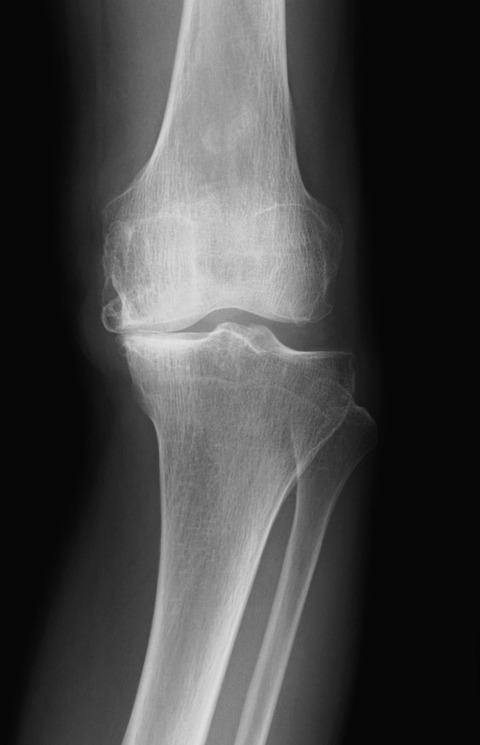

体重・荷重のかかる関節や頚椎・胸椎・腰椎は早ければ20代から静かに変形が始まります。

レントゲン画像上の変形は症状の原因というよりも、筋肉の機能低下の結果生じると考えるほうがよいと思われます。

痛くなくても画像上の変形は残っているどころか、時間の経過とともに変形がさらに進むことが多いです。

「痛くないから通院をやめた」という方が、自覚症状を伴わずに時間が経過したところで以前よりも強い痛みを自覚して、再び来院したら変形が相当進んでいたというケースは珍しくありません。